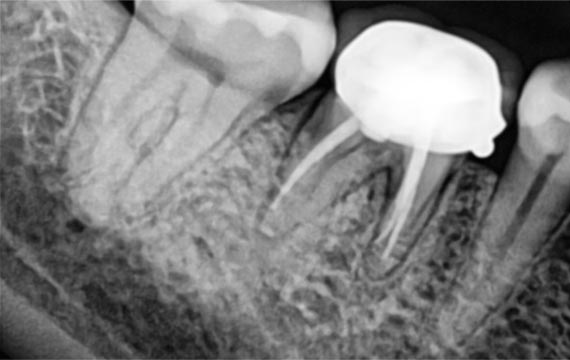

시술 전후 비교

BEFORE

down

AFTER